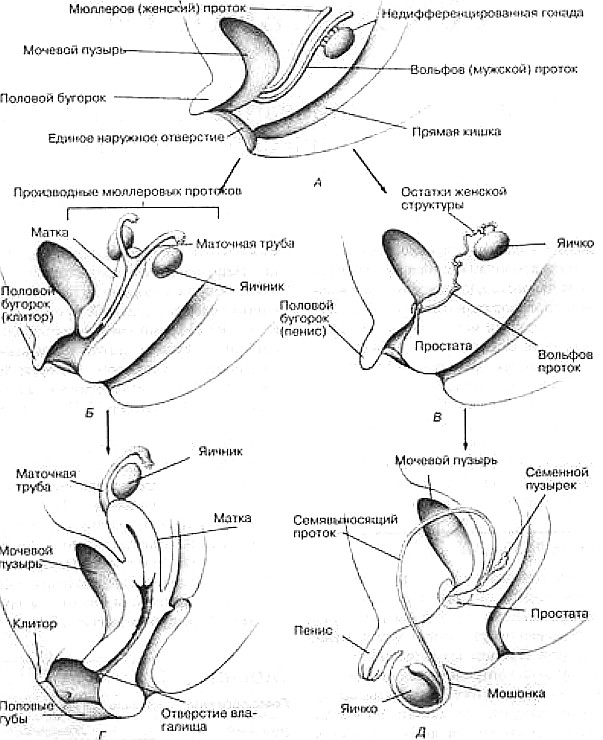

Несмотря на различие генетических кодов, развитие мужского и женского эмбрионов на протяжении первых недель с анатомической точки зрения происходит одинаково. На пятой и шестой неделе беременности формируются первичные половые железы, сначала в форме тканевой складки, а затем в виде более четко выраженных структур. На этой стадии гонады бипотенциальны, т.е. могут развиться в яички или яичники в зависимости от условий формирования

В это же время у мужского и женского эмбрионов развиваются две первичные парные

системы протоков: мюллеровы протоки и вольфовы протоки

В это же время у мужского и женского эмбрионов развиваются две первичные парные

системы протоков: мюллеровы протоки и вольфовы протоки

(А) Недифференцированная закладка в возрасте примерно 6-7нед. (Б) Состояние женских половых органов у 14-неделъного плода. (В) Состояние мужских половых органов у 14-недельного плода.(Г) Состояние женских половых органов у 40-недельного плода. (Д) Состояние мужских половых органов у 40-неделъного плода.

У эмбрионов мужского пола на восьмой неделе после зачатия только что сформировавшиеся яички начинают секретировать два разных вещества. Одно из них, называемое ингибитором мюллеровых протоков, вызывает их атрезию и практически полное исчезновение (вместо превращения в женские внутренние половые органы). Одновременно образуется тестостерон, который стимулирует развитие вольфовых протоков в эпидидимис, семявыносящие и семявыбрасывающие протоки, а также семенные пузырьки . В некоторых тканях тестостерон преобразуется в другое соединение - дигидротестостерон, стимулирующий развитие полового члена, мошонки и предстательной железы (Imperato-MeGinley, Peterson, 1976).

Тестостерон и дигидротестостерон являются андрогенами, т.е. маскулинизирующими гормонами. В отличие от мужчин половая дифференцировка у женщин не контролируется гормонами. Яичники обычно формируются примерно на двенадцатой неделе после зачатия, но даже если этого не происходит, мюллеровы протоки все равно развиваются в матку, маточные трубы и внутреннюю треть влагалища (Money, Ekrhardt, 1972).

В отсутствие больших количеств тестостерона, который мог бы стимулировать сохранение вольфовых протоков, последние редуцируются и обнаруживаются у женщин в виде малозаметных остаточных образований. К четырнадцатой неделе развития мужские и женские эмбрионы имеют совершенно разные по строению внутренние половые органы